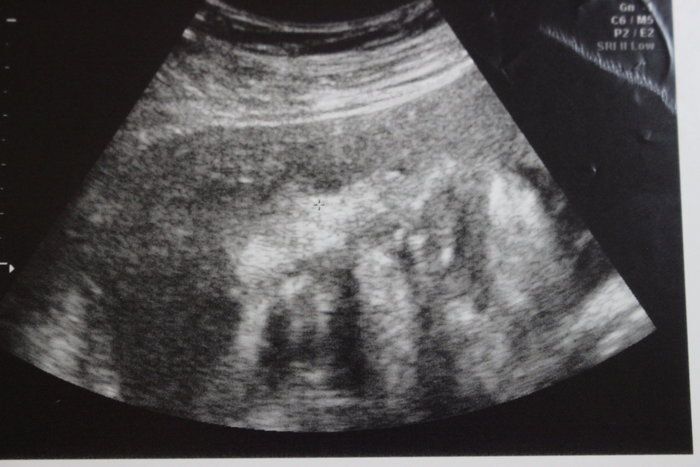

小吉さんの妊娠32週目のエコー写真

思いがけず授かった2人目は43歳の高齢出産!健診は不安と期待との板挟み!

赤ちゃんの背骨と肋骨がしっかりとできていることが確認できました。「小さいのにちゃんとあるな、頑張っているな」と感動したのを覚えています。